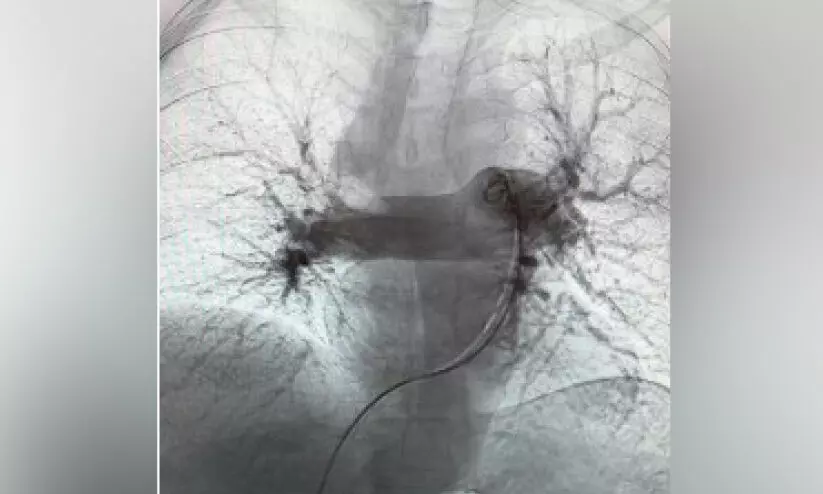

പ​ൾ​മ​ണ​റി എം​ബോ​ളി​സ​വും വെ​ന​സ് ത്രോം​ബോ​ബോ​ളി​സ​വും ചി​കി​ത്സി​ക്കു​ന്ന​തി​നു​ള്ള അ​ത്യാ​ധു​നി​ക ഇ​ന്റ​ർ​വെ​ൻ​ഷ​ന​ൽ സാ​ങ്കേ​തി​ക​വി​ദ്യ​യാ​ണ് ആ​ൽ​ഫ​വാ​ക് സി​സ്റ്റം. തു​റ​ന്ന ശ​സ്ത്ര​ക്രി​യ​യു​ടെ ആ​വ​ശ്യ​മി​ല്ലാ​തെ വ​ലി​യ സി​ര​ക​ളി​ൽ​നി​ന്ന് ര​ക്തം ക​ട്ട​പി​ടി​ക്കു​ന്ന​ത് കാ​ര്യ​ക്ഷ​മ​മാ​യി നീ​ക്കം​ചെ​യ്യാ​ൻ ഇ​ത് പ്രാ​പ്ത​മാ​ക്കു​ന്നു.

പ്രാ​ദേ​ശി​ക, അ​ന്ത​ർ​ദേ​ശീ​യ മെ​ഡി​ക്ക​ൽ സ​മൂ​ഹ​ത്തി​ൽ ആ​ശു​പ​ത്രി​യു​ടെ പ​ദ​വി മെ​ച്ച​പ്പെ​ടു​ത്തു​ന്ന​തി​നു​ള്ള ഒ​മാ​ന്റെ വി​ശാ​ല​മാ​യ കാ​ഴ്ച​പ്പാ​ടു​മാ​യി ഇ​ത് യോ​ജി​ക്കു​ന്നു. എ​ക്സ്-​റേ മാ​ർ​ഗ​നി​ർ​ദേ​ശ​ത്തി​ൽ ഫെ​മ​റ​ൽ സി​ര​യി​ലേ​ക്ക് ഒ​രു ക​ത്തീ​റ്റ​ർ ഘടിപ്പിച്ചാണ് ഈ ​ന​ട​പ​ടി​ക്ര​മം ന​ട​ത്തു​ന്ന​തെ​ന്നും ര​ക്ത​ന​ഷ്ടം കു​റ​ക്കു​ന്ന ഒ​രു പ്ര​ത്യേ​ക നി​യ​ന്ത്ര​ണ ഉ​പ​ക​ര​ണം ഉ​പ​യോ​ഗി​ച്ച് ര​ക്തം ക​ട്ട​പി​ടി​ക്കു​ന്ന​ത് നീ​ക്കം ചെ​യ്യു​മെ​ന്നും സം​ഘം വി​ശ​ദീ​ക​രി​ച്ചു.

തു​റ​ന്ന ശ​സ്ത്ര​ക്രി​യ​യി​ൽ നി​ര​വ​ധി മ​ണി​ക്കൂ​റു​ക​ൾ ആ​വ​ശ്യ​മാ​ണ്. ഈ ​നൂ​ത​ന ചി​കി​ത്സ സം​വി​ധാ​ന​ത്തി​ൽ ഏ​ക​ദേ​ശം 30 മു​ത​ൽ 60 മി​നി​റ്റ് വ​രെ എ​ടു​ക്കു​ക​യു​ള്ളു. രോ​ഗി​ക്ക് 24 മ​ണി​ക്കൂ​റി​നു​ള്ളി​ൽ തീ​വ്ര​പ​രി​ച​ര​ണ​ത്തി​ൽ​നി​ന്ന് പു​റ​ത്തു​പോ​കാ​നും സാ​ധി​ക്കും. ര​ക്തം ക​ട്ട​പി​ടി​ക്കു​ന്ന​ത് നീ​ക്കം ചെ​യ്യു​ന്ന​തി​ൽ ഈ ​സാ​ങ്കേ​തി​ക​വി​ദ്യ 90 ശ​ത​മാ​ന​ത്തി​ല​ധി​കം വി​ജ​യ​ശ​ത​മാ​നം കൈ​വ​രി​ച്ച​താ​യും സ​ങ്കീ​ർ​ണ​ത​ക​ളി​ലും ര​ക്ത​സ്രാ​വ​ത്തി​ലും ഗ​ണ്യ​മാ​യ കു​റ​വ് വ​രു​ത്തി​യ​താ​യും മെ​ഡി​ക്ക​ൽ സം​ഘം റി​പ്പോ​ർ​ട്ട് ചെ​യ്തു.